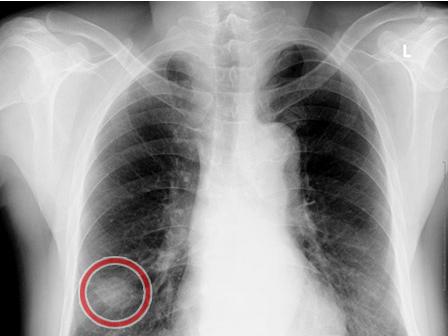

肺癌的胸片

肺癌的胸片,

中央型肺癌的横s或者反s征,是指右侧中央型肺癌的正位x光胸片上的典型

正常的胸片图